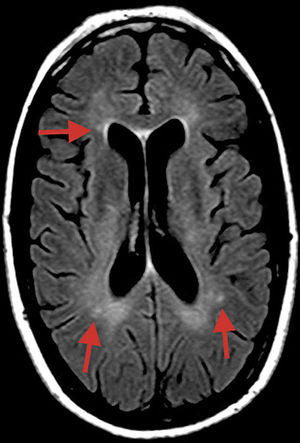

A T2-weighted FLAIR sequence obtained at symptom onset revealed small, nonspecific hyperintensities in the subcortical white matter, corpus callosum, and cerebellar peduncles (Fig. 1).

MRI may be helpful for early diagnosis in some cases, revealing microinfarcts in the central region of the corpus callosum in sagittal FLAIR and T2-weighted sequences; lesions typically resemble “snowballs,” and subsequently progress to black holes and atrophy. Lesions measure 3-7mm, suggesting occlusion of precapillaries of less than 0.1mm (100μm) in diameter. Microinfarcts may take the form of linear or “spoke” lesions. Diffusion sequences may also reveal hyperdense lesions to the internal capsule, resembling a “string of pearls.” The presence of these imaging findings in addition to lesions to the central region of the corpus callosum is pathognomonic of SS.2 However, most patients with SS show no MRI alterations.3